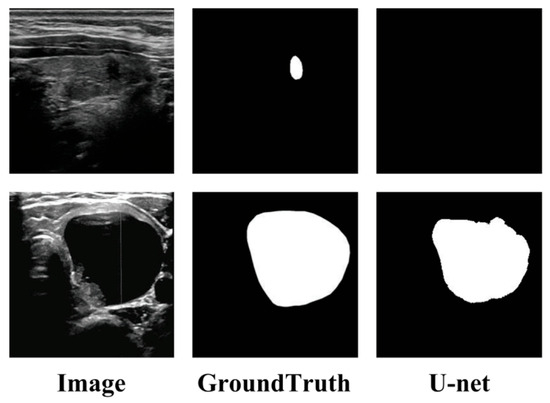

Prediction Multiscale Cross-Level Fusion U-Net with Combined Wavelet Convolutions for Thyroid Nodule Segmentation

The precise segmentation of thyroid nodules in ultrasound images is essential for computer-aided diagnosis and treatment. Although various deep learning methods have been proposed, similar intensity distributions and variable nodule morphology often lead to blurred segmentation boundaries and missed detection of small nodules. [...] Read more.

The precise segmentation of thyroid nodules in ultrasound images is essential for computer-aided diagnosis and treatment. Although various deep learning methods have been proposed, similar intensity distributions and variable nodule morphology often lead to blurred segmentation boundaries and missed detection of small nodules. To address this problem, we propose a multiscale cross-level fusion U-net with combined wavelet convolutions (MCFU-net) for thyroid nodule segmentation. Firstly, the network designs a multi-branch wavelet convolution (MBWC) block, which decouples texture features through wavelet domain multiresolution analysis and reorganizes cross-channel features, thereby enhancing context extraction and aggregation capabilities during the encoding stage. Secondly, a scale-selective atrous pyramid (SSAP) module based on multi-level dynamic perception is constructed to achieve saliency enhancement for nodules of varying sizes, in order to improve the detection ability for small nodules. Thirdly, to decrease the loss of fine-grained information during upsampling, a cross-level fusion module (CLFM) with hierarchical refinement mechanisms is designed, which progressively reconstructs ambiguous boundary areas through multistage upsampling. Experiments conducted on two public ultrasound datasets, TN3K and DDTI, demonstrate the effectiveness and superiority of our method, achieving Dice coefficients of 85.22% and 78.21% and IoU values of 74.25% and 64.23%, respectively. Full article